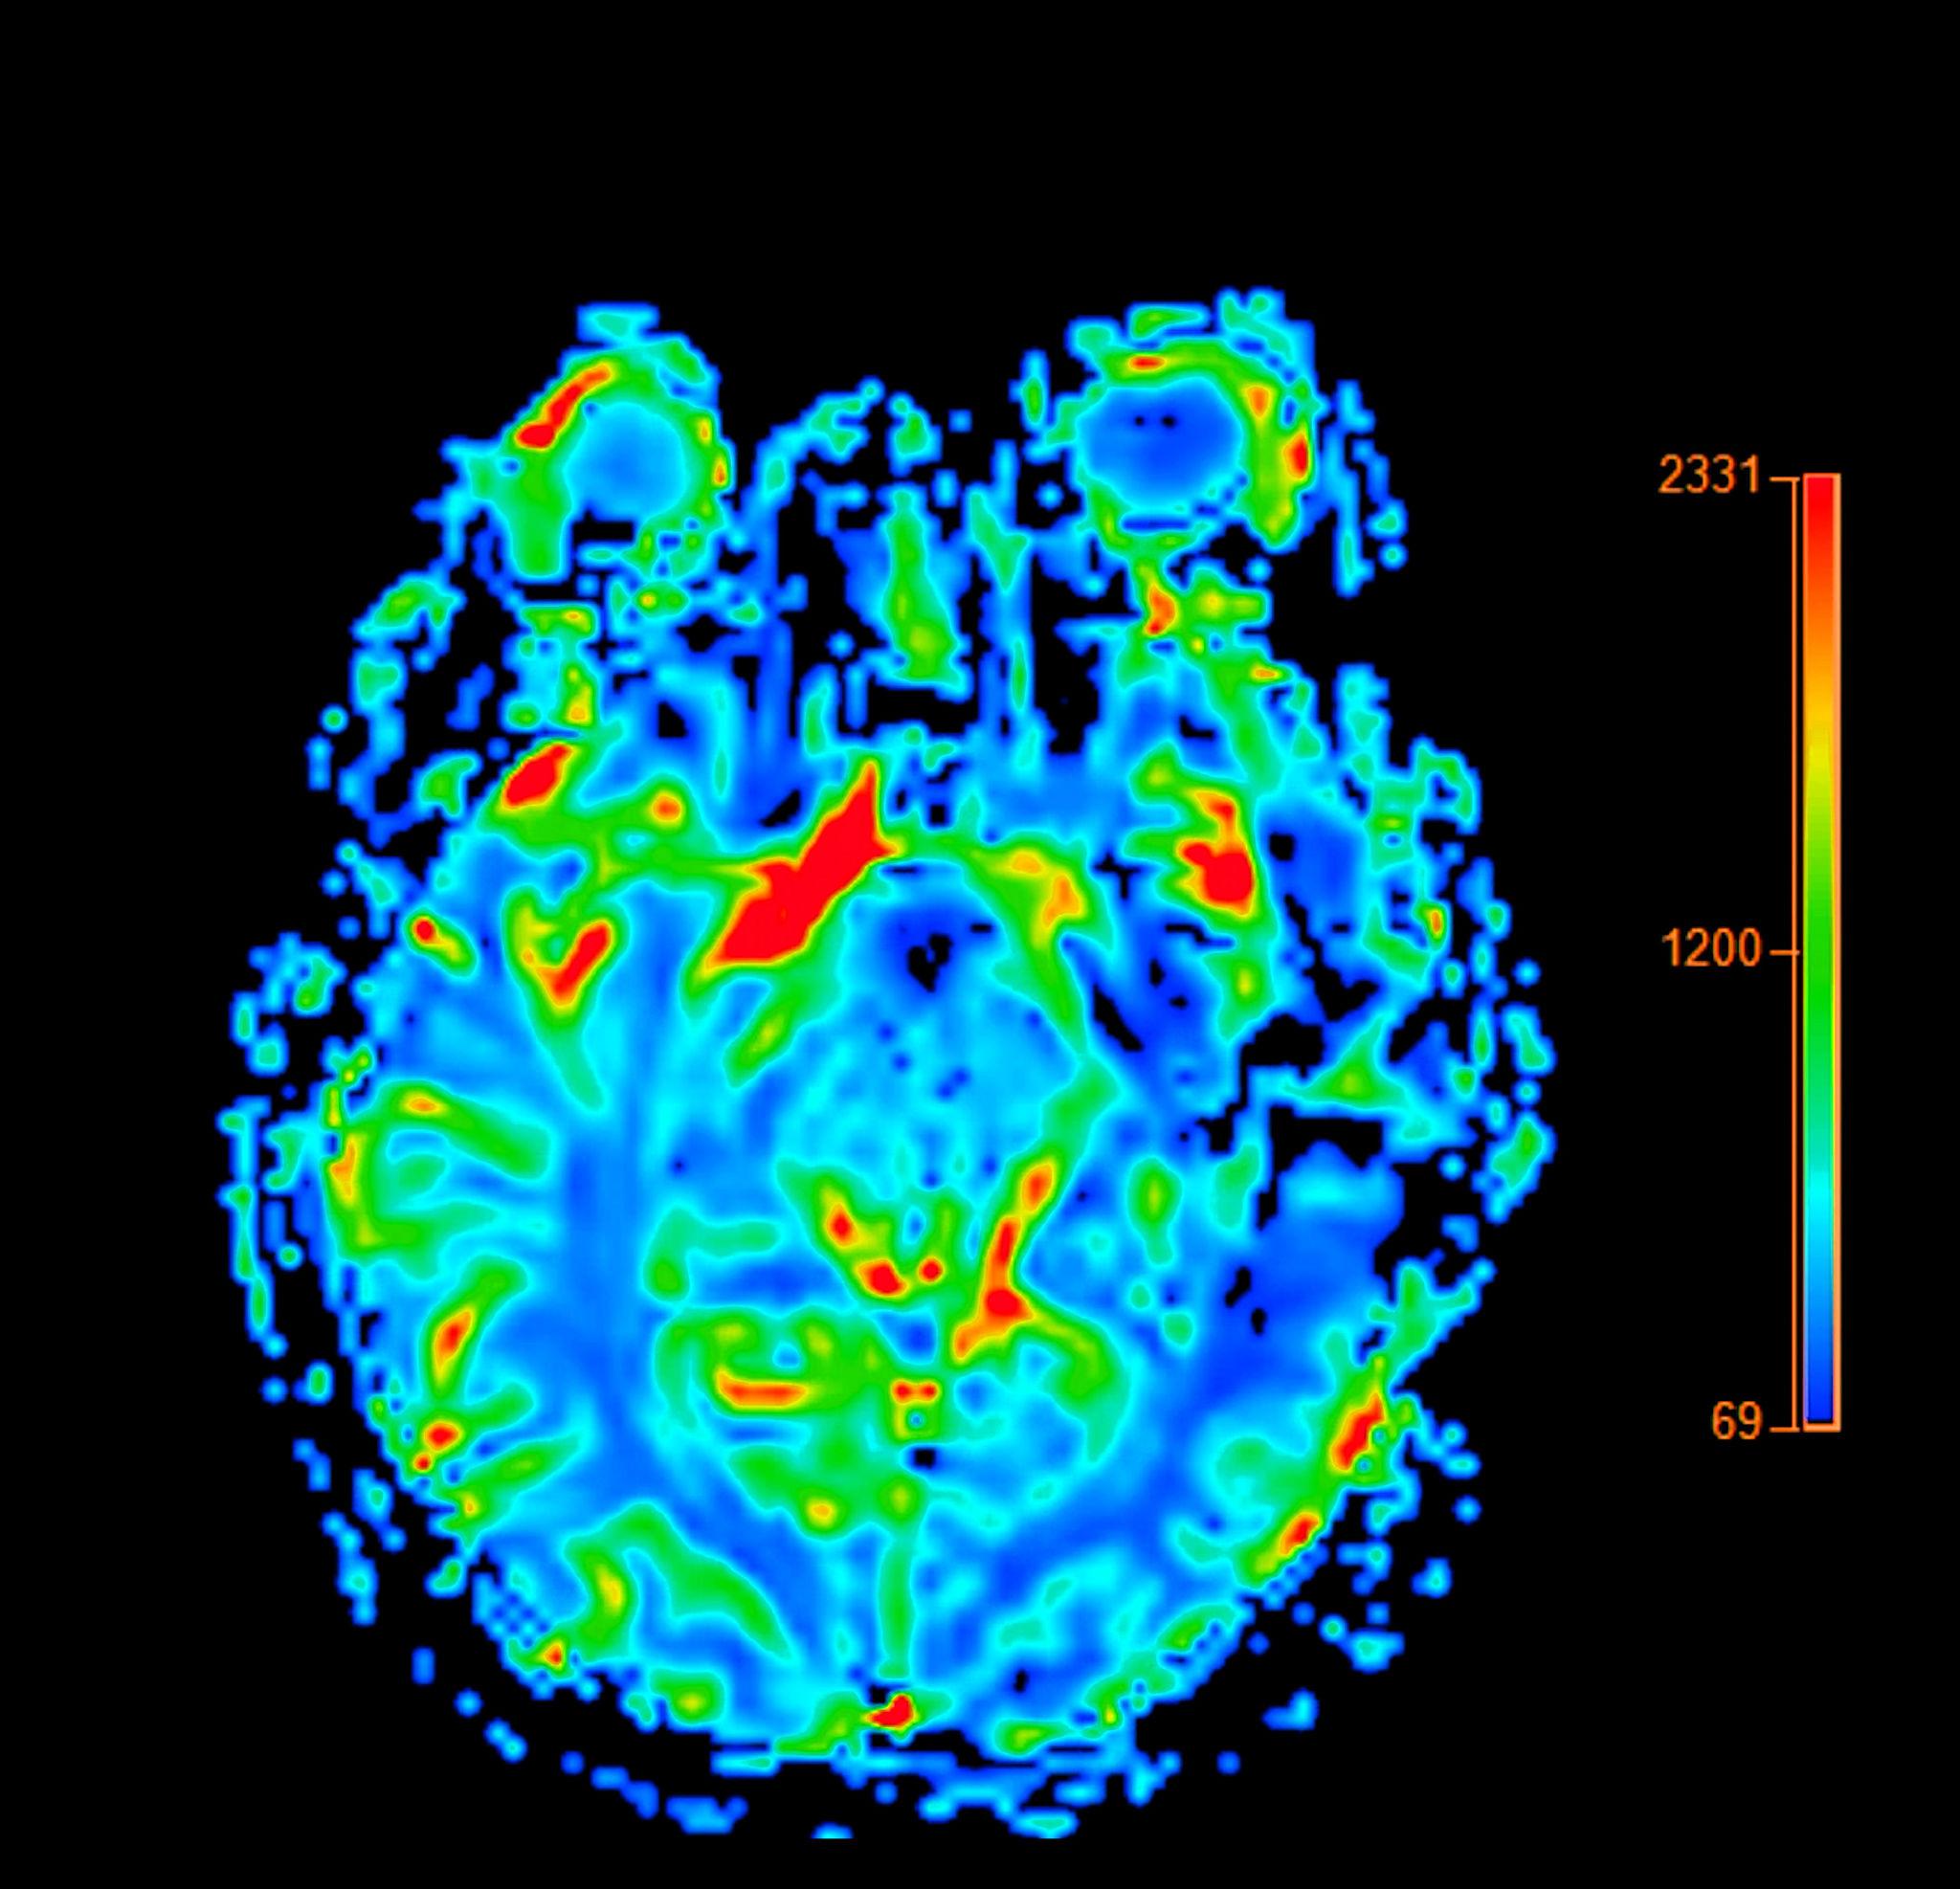

High-resolution EEG brain mapping

Machine learning–driven pattern recognition

Adaptive treatment optimization

Data-driven

Personalized